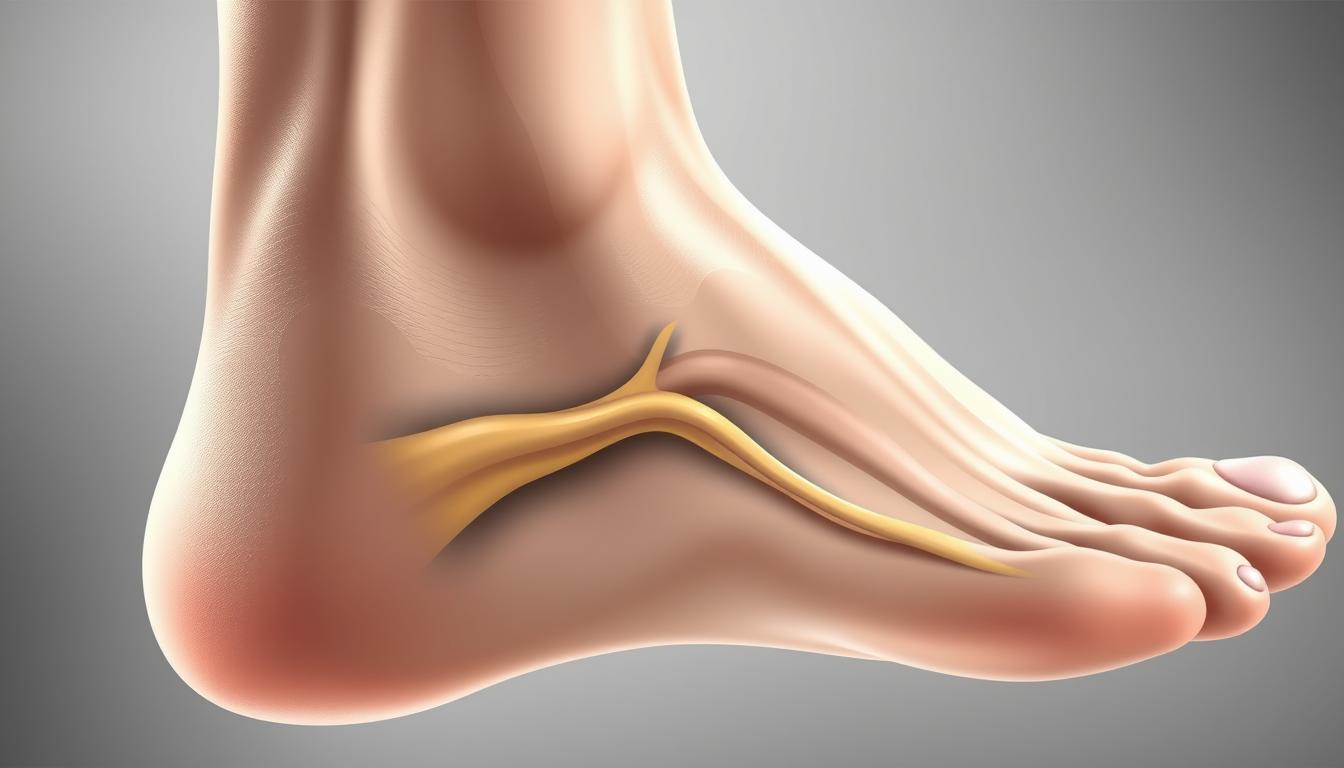

Mięsień strzałkowy czwarty i „niski” brzusiec mięśnia strzałkowego krótkiego a niestabilność funkcjo

Czy jesteś pewien, że znasz wszystkie aspekty anatomiczne mięśni strzałkowych, które mogą wpływać na…

Czy kiedykolwiek zastanawiałeś się, dlaczego u niektórych osób występuje wystająca kość na stopie, a…